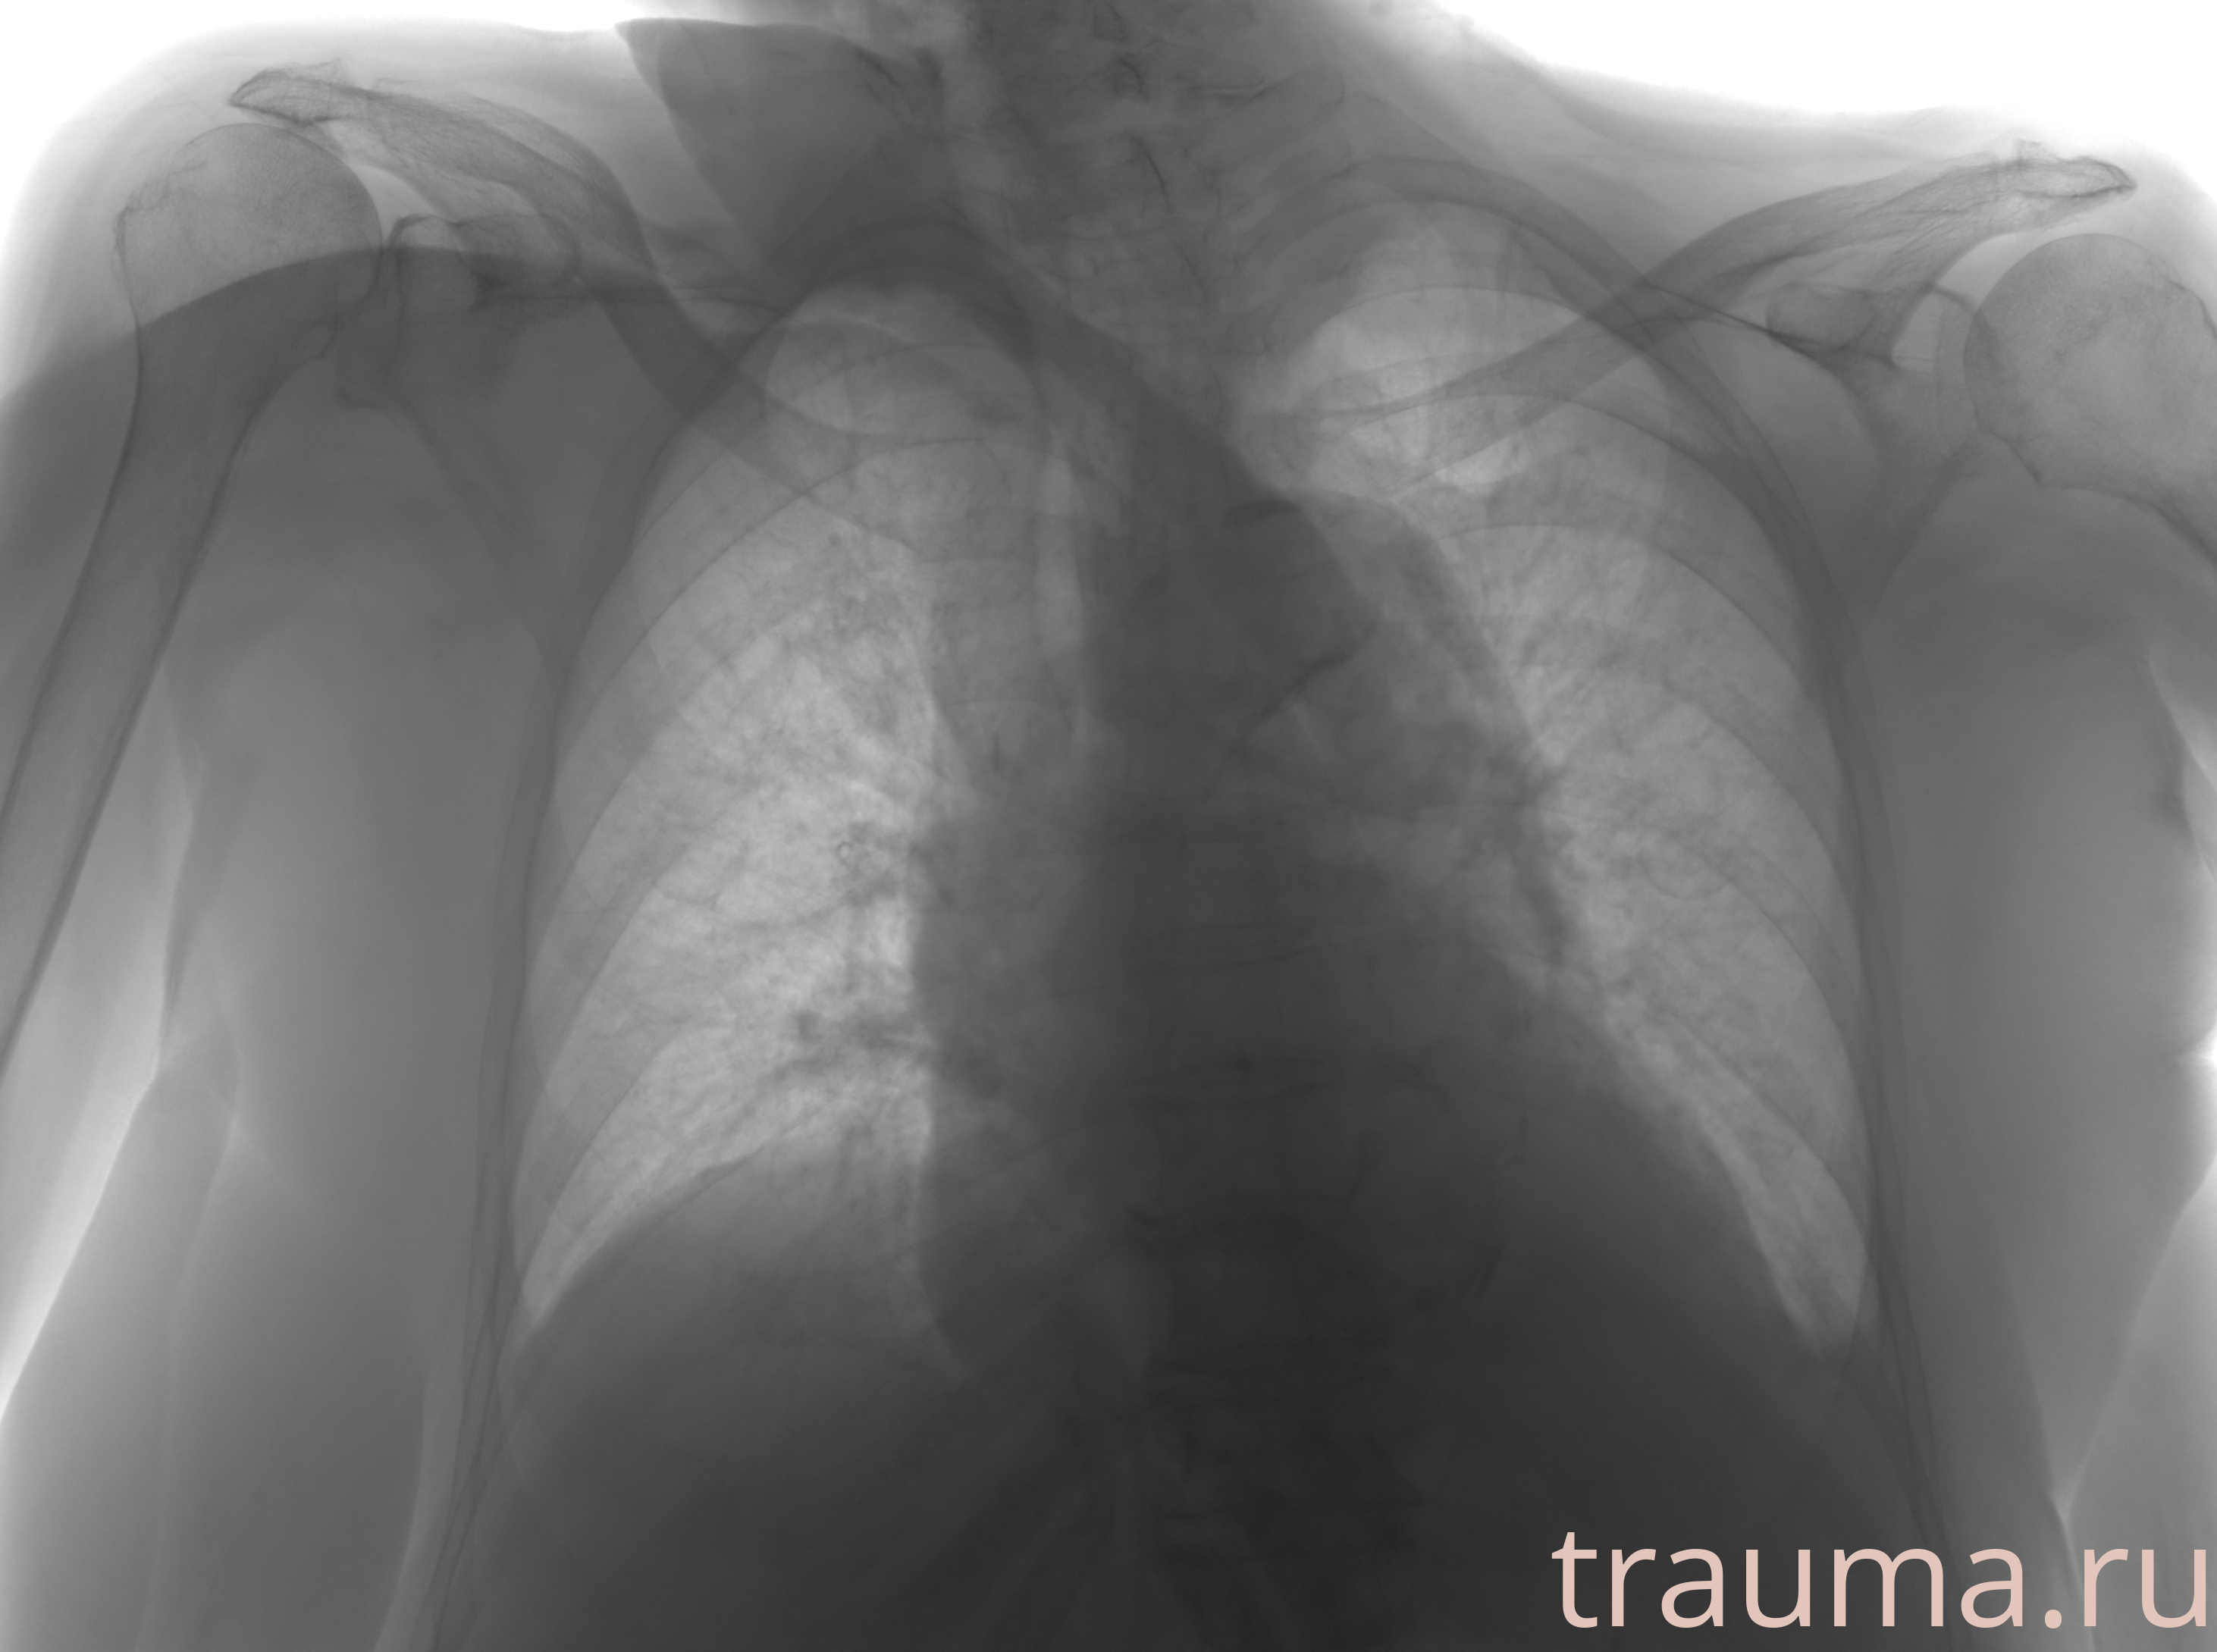

Рентгенограммы

Рентген на дому: по вашему адресу приезжает врач-рентгенолог, травматолог-ортопед с мобильным рентгеновским аппаратом, проводит диагностику травмы или заболевания, делает необходимые рентгенограммы, дает рекомендации по дальнейшему лечению. Получить качественные снимки в домашних условиях возможно благодаря уникальной методике, разработанной МосРентген Центром для института  Склифосовского